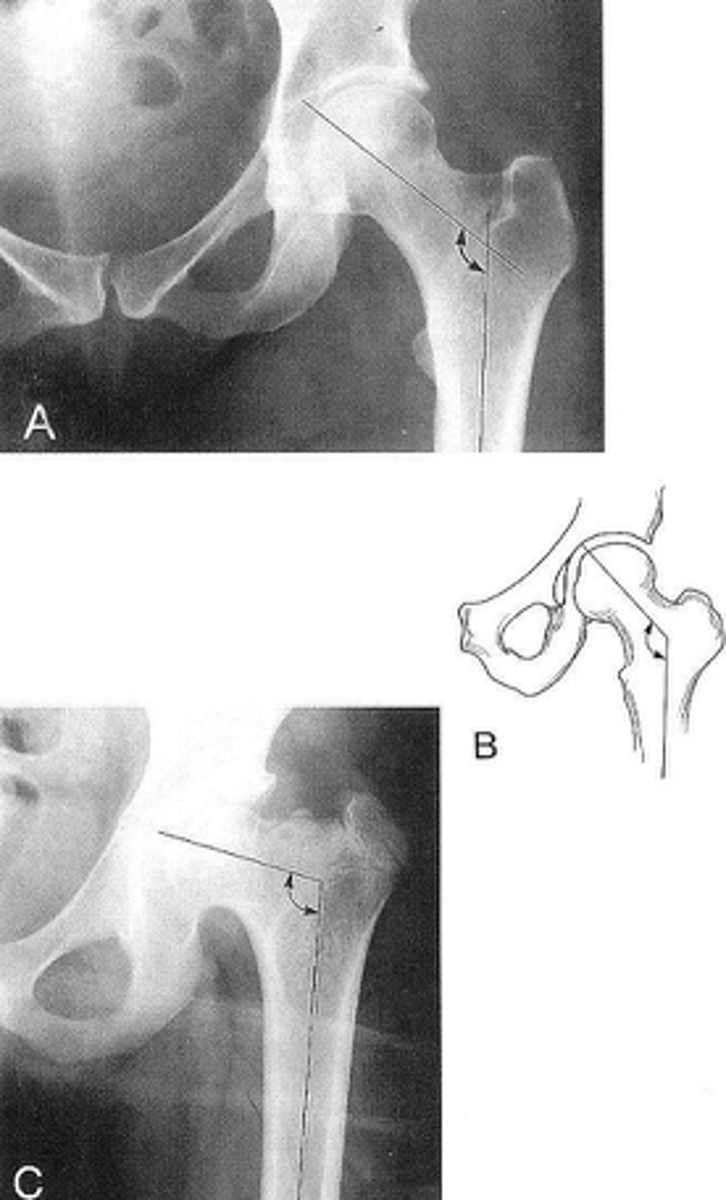

11

New cards

Unilateral AP hip

ID standard unilateral hip projection

<p>ID standard unilateral hip projection</p>

12